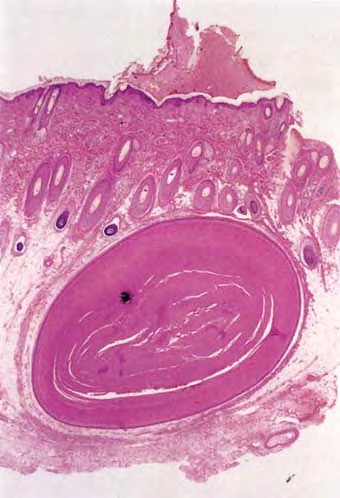

Trichilemmal cyst = كيسة غمد الشعرة